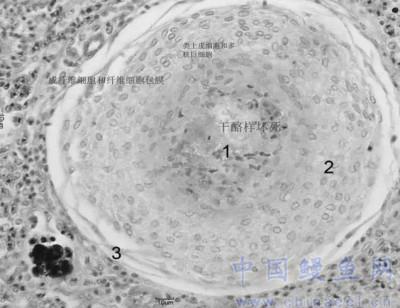

坏死灶典型的三层固定结构

诺卡氏菌病:对病灶进行病理切片观察可发现各内脏器官存在大量的结节性坏死灶,且该坏死灶具有典型的三层固定结构。同时也可发现串珠样诺卡氏菌体。

迟缓爱德华氏菌病:对病灶进行病理切片观察不具有典型的三层固定结构,有时可发现多处坏死灶(如图中画圈处)和黑色素巨噬细胞中心。(作者:高雪文)